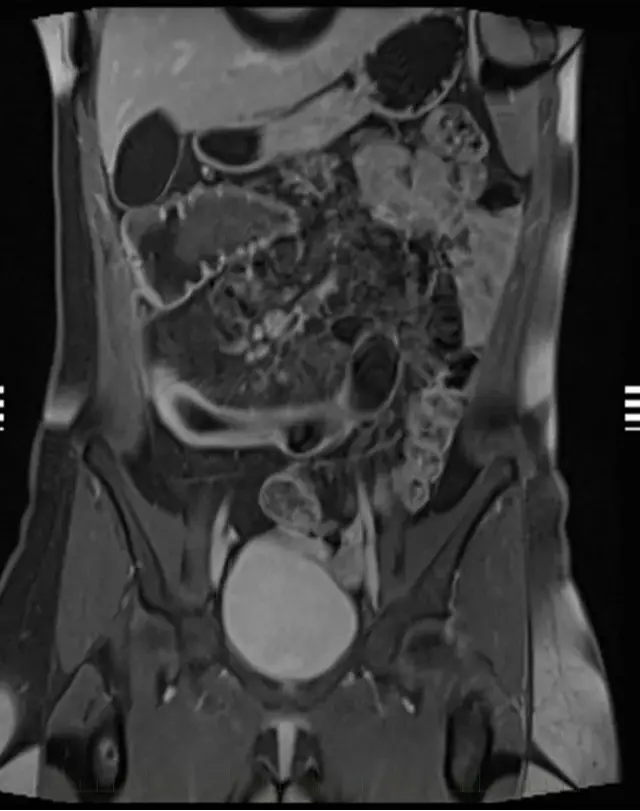

МРТ энтерография (тонкого кишечника с контрастом)

МРТ энтерография – это МРТ тонкого кишечника.Для чего: помогает выявить воспаления, полипы, опухоли и другие патологии кишечника.